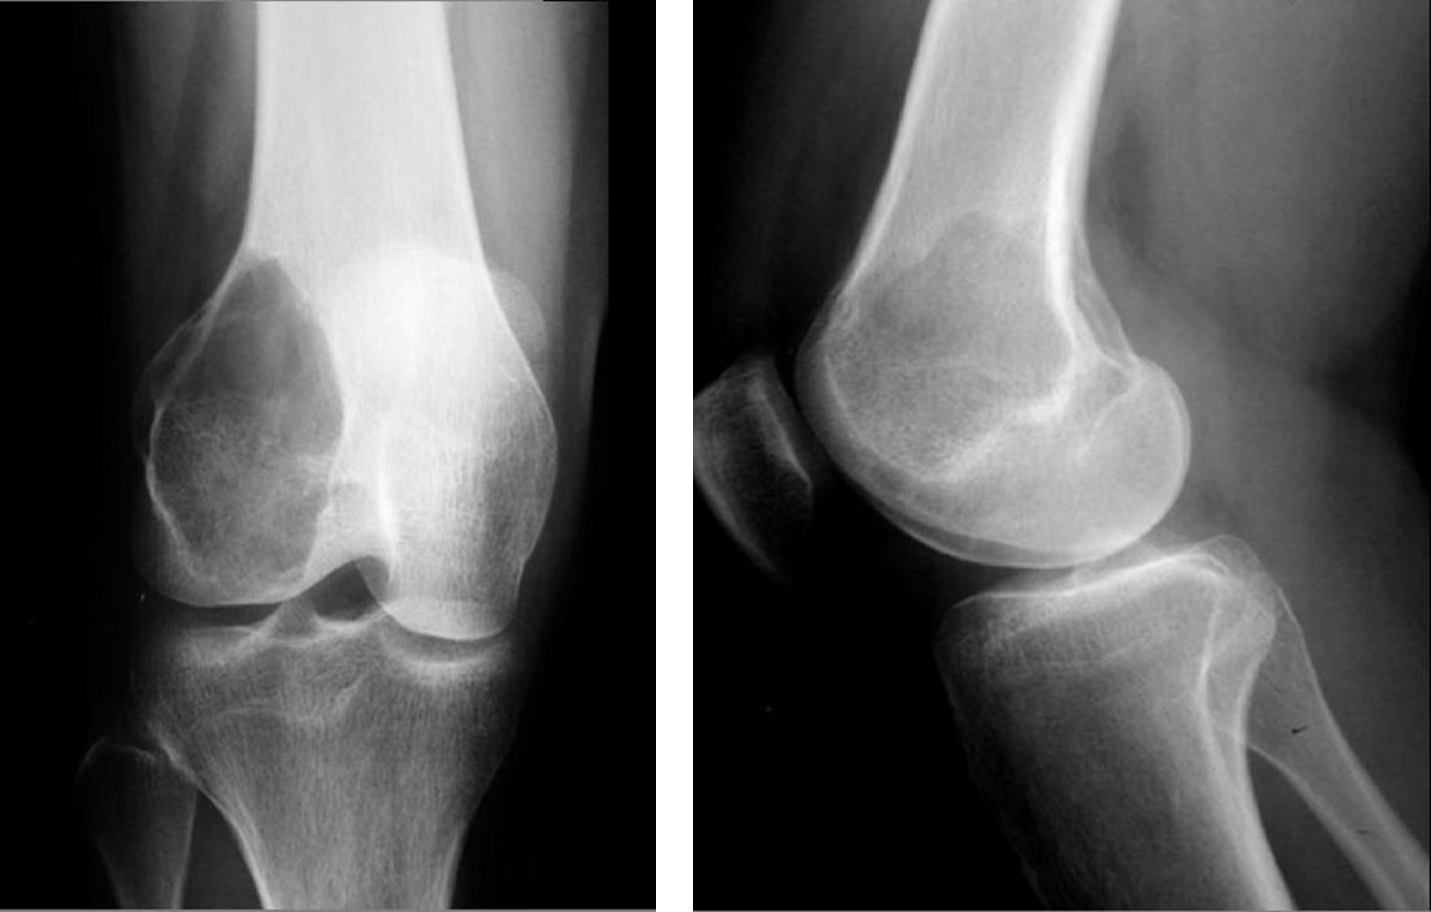

Adult patient: Giant cell Tumor. Expansile lytic lesion eccentric location The subarticular position is characteristic of this tumour.

Adult : Expansile lytic lesion, eccentric in the metaphysis. Sub articular surface May violate the cortex . Aggressive nature